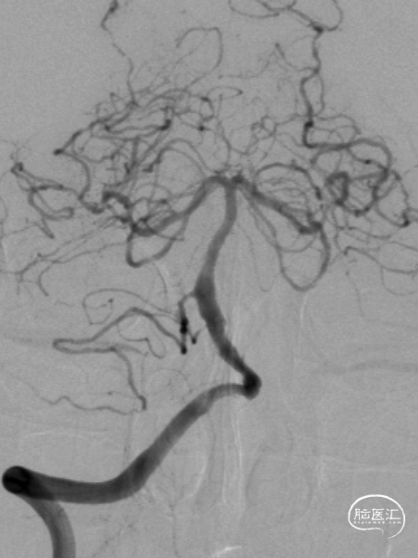

右侧桡动脉穿刺造影:右侧椎动脉优势;左侧椎动脉发自弓上,纤细迂曲;双侧后交通动脉欠发达。

超选右侧椎动脉造影:右侧椎-基底动脉连接处次全闭塞,前向血流 mTICI 2b级。